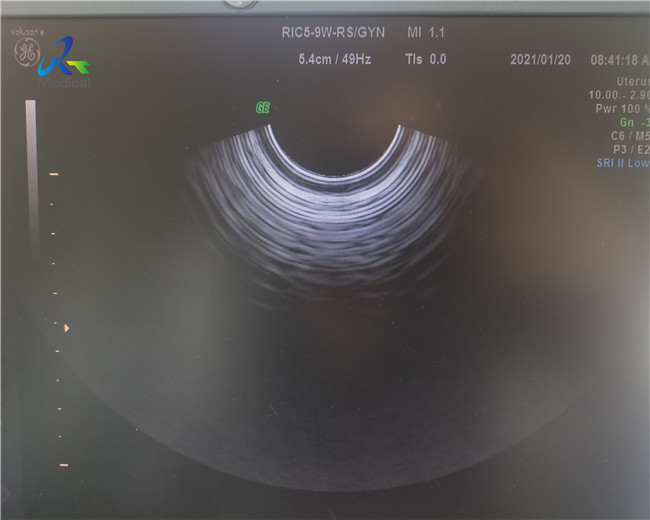

Замена Кристл зонда ультразвука GE RIC5-9A-RS 4D

Изменение первоначальное Кристл зонда GE RIC5-9A-RS 4D

Линии показывая вверх на экране: Дефекты зонда ультразвука аппаратные неисправности датчика ультразвука обнародуя как различные ненормальности изображения развертки, в строгих случаях даже причиняя полную потерю сигнала. Эти форма артефакта ультразвука.

Поэтому, осведомленность различных знаков повреждения оборудования критическая. Было показано что регулярный контроль картины реверберации в-воздуха зондов ультразвука обнаруживает большую пропорцию повреждения оборудования, и результаты долгосрочной носки 1. датчика. Оно также осторожен осторожно определить картину реверберации для каждого заново приобретенного зонда, как дефекты при изготовлении часто очевидные как подобные артефакты.

Диагностика: Замените первоначальный кристалл, и изображение будет нормальным.